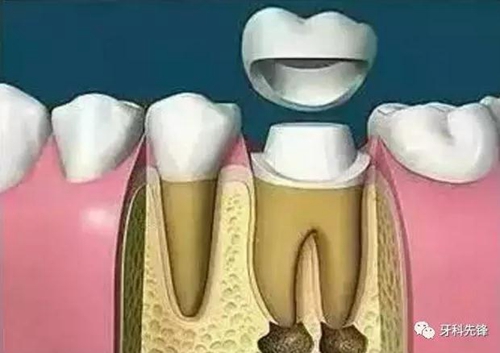

8、完成牙體修復(fù)

X線片顯示根管充填完好,行暫時(shí)或永久牙體修復(fù),帶上牙冠,保護(hù)患牙。至此根管治療才可算完成,同時(shí)根管治療后還需復(fù)診,一般周期可為3個(gè)月、半年、1年、2年或更長。

根管治療后建議做牙套修復(fù)

做完了根管治療后,醫(yī)生會建議患者做一個(gè)牙套。許多患者因此產(chǎn)生疑問:我的牙齒不痛不就治好了嗎,為什么還要做牙套呢?

其實(shí),牙齒在做完根管治療后,牙髓已經(jīng)被清理,只剩下空殼;牙齒在缺乏牙髓的營養(yǎng)供應(yīng)下會變得易脆和易斷裂。此時(shí),為了保護(hù)牙齒,醫(yī)生就會制作一個(gè)牙冠,把牙齒保護(hù)起來。